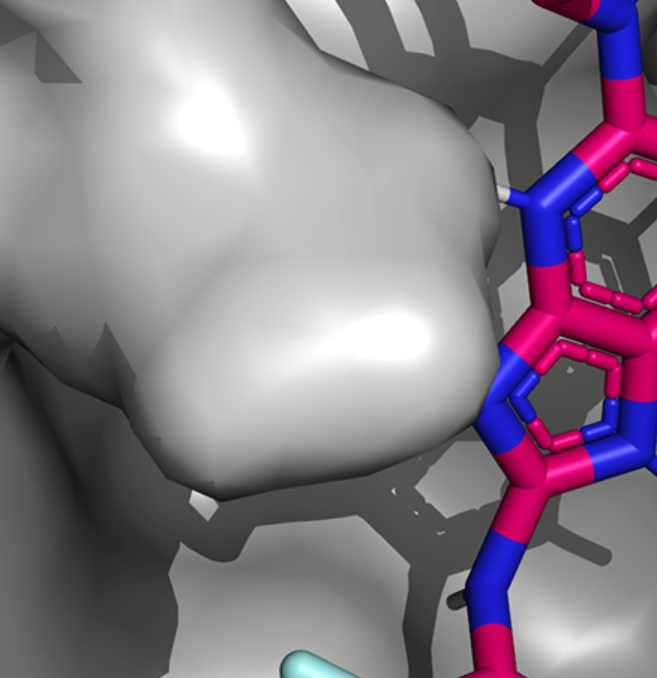

El Servicio BioNeMo LLM suma dos nuevos modelos de idiomas BioNeMo para aplicaciones de química y biología. Proporciona soporte para datos de proteínas, ADN y bioquímica.

BioNeMo permite a los investigadores ampliar el alcance de su trabajo con modelos que contienen miles de millones de parámetros. «Estos modelos más grandes pueden almacenar más información sobre la estructura de las proteínas, las relaciones evolutivas entre los genes e incluso generar nuevas biomoléculas para aplicaciones terapéuticas», aclaran desde Nvidia.